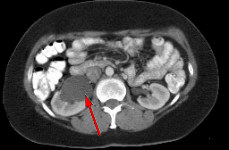

Fig.1 Fig.2 Fig.3

FINDINGS: The ultrasound (not shown) demonstrated dilated collecting system versus extrarenal pelvis on the right. Fig. 1 and Fig. 2 are nephrographic and delayed images through the kidneys. They demonstrate a large dilated right renal pelvis (red arrows) with urine-contrast level and a normal-sized ureter consistent with UPJ obstruction. Fig. 3 is a 3D image from a renal MRA showing an accessory right renal artery (yellow arrows) supplying the right lower pole and impressing upon the right UPJ, explaining the UPJ obstruction. Normal renal arteries are also clearly seen (green arrows)